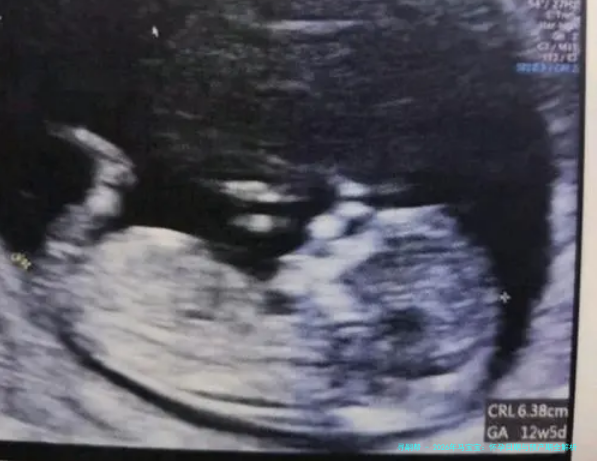

首先,让我们简单回顾一下怀孕和预产期的计算方法。通常,预产期是从末次月经的第一天算起,加上280天(约40周)。这只是一个估算,实际分娩日期可能会提前或推后一两周。为什么是280天呢?因为这是人类妊娠的平均周期,考虑了卵子受精和胎儿发育的过程。举个例子,如果一位准妈妈的末次月经是2025年5月10日,那么她的预产期大约是2026年2月14日左右。不过,每个人的身体状况不同,建议结合B超检查来调整预产期。